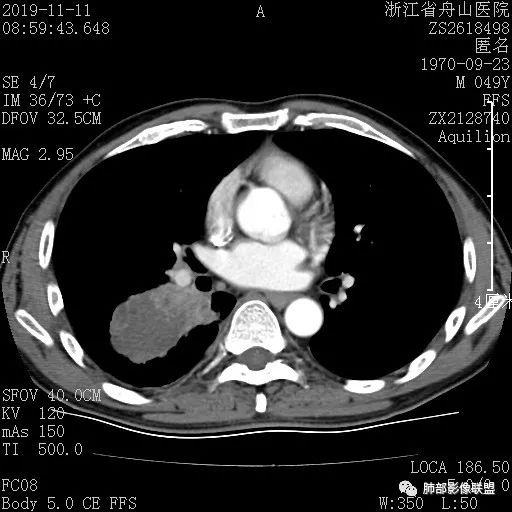

一眼识破的肺部新生物4例CT影像讨论

case 1 医学百科网 | YxBaike.Com

病理结果

浸润性腺癌 医学百科网 | YxBaike.Com

病理结果没有记录附壁生长的成分。我认为附壁生长为主型LPA。通常收缩力明显的,是裂隙状胸膜凹陷 但在肺尖部,可能胸膜有一定的壳样增厚,所以可以圆洞样 医学百科网 | YxBaike.Com

一句话小结:

胸膜下孤立较大混合密度结节影,中央实行密度,周围磨玻璃边界清楚提示存在小叶间隔阻挡。局部明显胸膜凹陷,提示病灶较强收缩能力,这也很少见于粘液腺癌。 医学百科网 | YxBaike.Com

综上更符合浸润性腺癌。